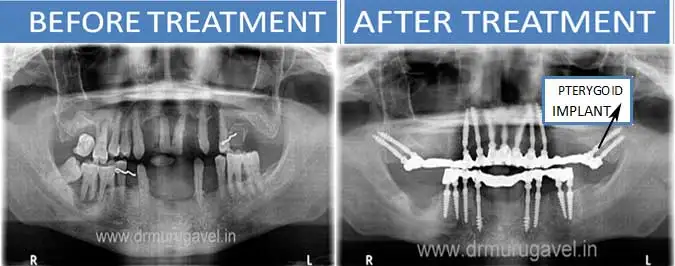

If you have been told by your dentist, that you have less bone or no bone in upper maxilla jaw, for dental implants, do not worry. These less bone situation can be successfully treated by pterygoid implants and fixed teeth can be given in 3-4 days.

Tubero pterygoid implants are indicated for patients who do not have enough bone for regular conventional implants. These implants are placed in the 2nd and 3rd molar region of the upper jaw.

– Avoids the need for sinus lift/bone grafts

– Helps to give fixed teeth in 3 days